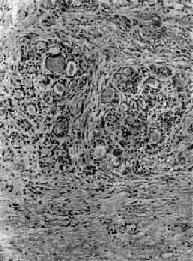

2.纤维性甲状腺炎(fibrous thyroiditis)又称Riedel甲状腺肿,甚少见,主要发生在中年妇女,病因不明。病变多从一侧开始,甲状腺甚硬,表面略呈结节状,与周围明显粘连,切面灰白。镜下,甲状腺滤泡明显萎缩,纤维组织明显增生和玻璃样变,有少量淋巴细胞浸润(图15-8)。临床常有甲状腺功能低下。

图15-8 纤维性甲状腺炎

甲状腺滤泡萎缩,纤维组织明显增生,有少量淋巴细胞浸润